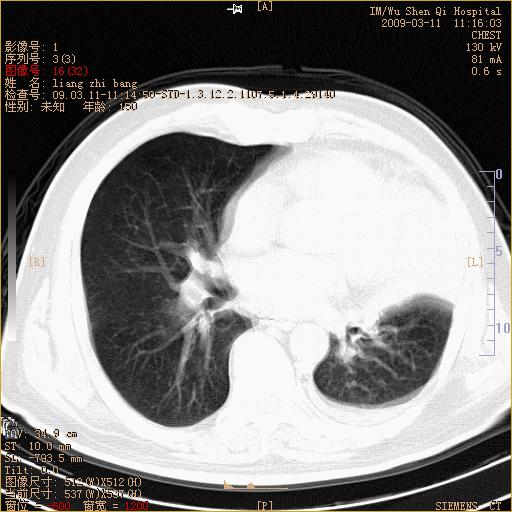

标题: CT18604:男,60岁,咳嗽一月余 [打印本页]

标题: CT18604:男,60岁,咳嗽一月余

1)考虑左肺上叶中央型肺癌并左肺上叶肺不张;建议必要时行纤支镜检查进一步明确诊断。2)左侧胸腔积液。

肺门肿块、支气管开口闭塞伴肺不张及胸水!典型的中心型肺癌变现!

1、左肺上叶中央型肺癌并上叶阻塞性肺不张。

2、左侧胸腔少量积液,右侧胸膜轻度增厚。

左肺们肿块并左肺上叶不张。考虑左肺中心性肺癌并左肺上叶不张及左侧胸腔积液